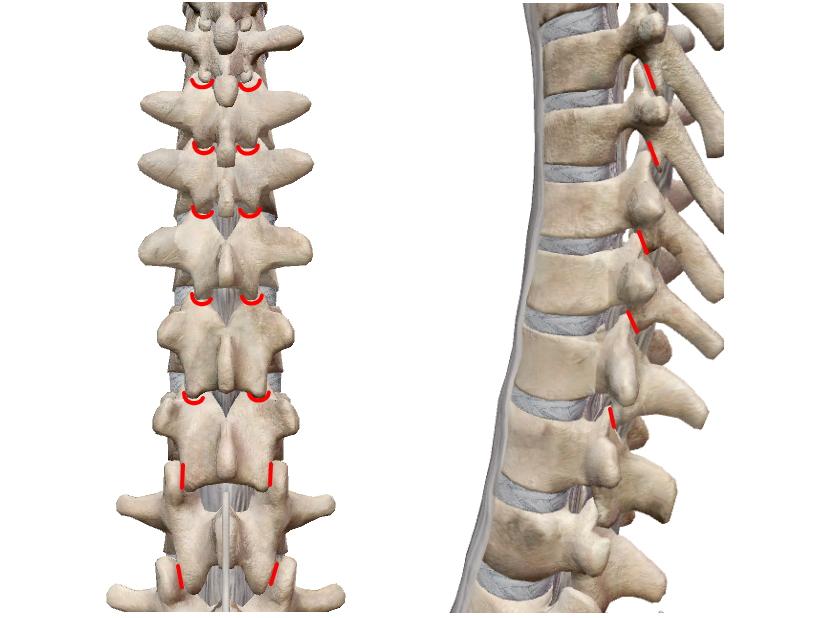

平面関節

| 平面に近い関節面が滑るように動く多軸関節。関節面が小さいので可動範囲は極めて小さい。 椎間関節、仙腸関節、肩鎖関節、脛腓関節、手根間関節、足根間関節、豆状骨関節。 *仙腸関節、脛腓関節は、関節面の半分が線維性軟骨結合が占め関節腔が非常に小さいので『半関節』とも。 |